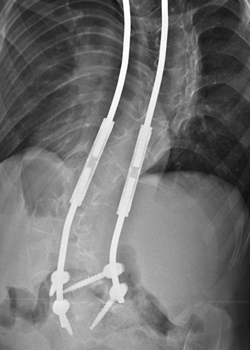

FOR IMMEDIATE RELEASE SURGEONS IMPLANT MAGNETIC GROWING RODS IN GROUNDBREAKING TREATMENT FOR EARLY-ONSET SCOLIOSIS The magnetic growing rods are attached to one or both sides of the spine. Following surgery, these rods can be lengthened non-invasively as the child grows using an external remote ... Return Document

Growing Spine Study Group Traditional Growing Rods Versus Magnetically -No previous spine surgery --> 2-year follow-up •17 MCGR patients met the inclusion criteria •12 of 17 patients had complete data available for analysis METHODS ... Return Doc

Traditional growing rods, which Chief of Pediatric Spine and Scoliosis Surgery at NewYork-Presbyterian/Morgan Stanley Children’s Hospital, the MAGEC [MAGnetic Expansion Control] device uses external magnets to control a rod implanted in the spine. ... Retrieve Full Source

Idiopathic scoliosis is a condition of a child’s spine. The spine has an abnormal side-to-side shaped curve that Surgery is recommended for children with curves greater techniques as magnetically controlled growing rods (MAGEC) and intraoperative navigation. Dr. ... Return Document